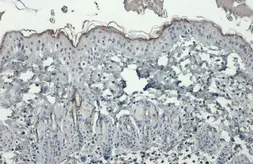

Images